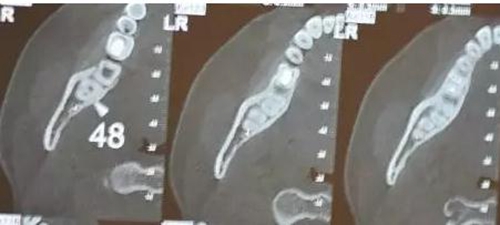

患者、女、24歲,主訴:右側(cè)下后牙自發(fā)疼數(shù)月。??茩z查:48垂直位、萌出約1/2,合面齲壞,探痛明顯,全景片檢查;48牙根與下頜管重疊,加拍CBCT檢查:下頜管位于48根尖下方的舌側(cè),牙根并未進(jìn)入下頜管內(nèi)。診斷:48中位垂直阻生伴牙髓炎。治療計(jì)劃:建議拔除48.患者同意治療方案,簽術(shù)前知情同意書。

圖4.CBCT的水平斷面檢查:48牙根不在下頜管內(nèi),但與下頜管緊鄰